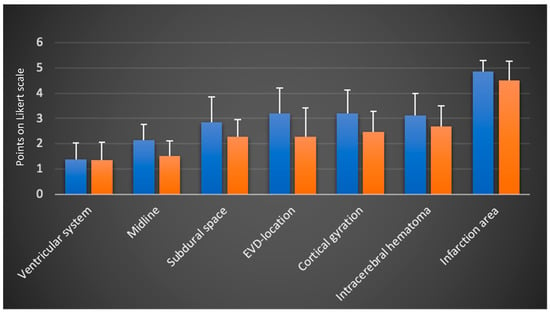

3.2. Evaluation and Comparison of the Resident and Attending Subgroup

A separate analysis and comparison of the two subgroups—residents and attending physicians—was conducted (Figure 3). In the separate evaluation, the more experienced attending physicians gave lower (better) ratings in all categories.

Figure 3.

Separated scores of residents (left column) and attending physicians (right column) (mean values and standard deviation on the Likert scale from 1: very good visualization to 5: insufficient visualization and 6 points: structure not found; N = 3 examiners; n = 158 TUS sessions).

The ranking trends among the imaging categories remained consistent. The mean ratings and differences between both groups are summarized in Table 2. The largest differences between the two subgroups were observed in the categories EVD location, cortical gyration and midline.